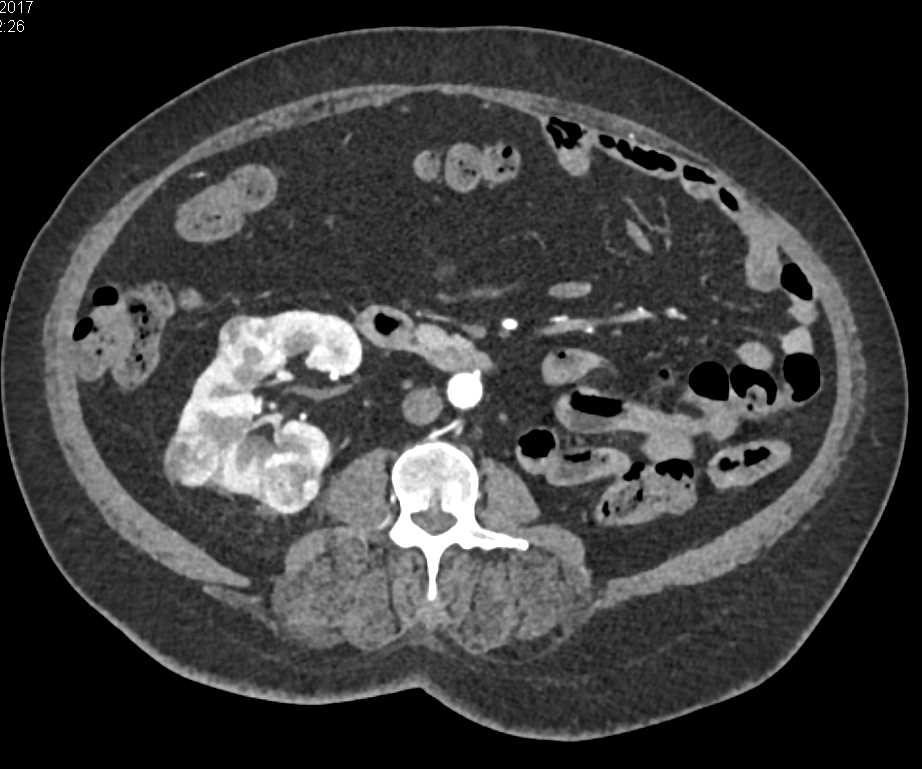

Angiomyolipoma Right Kidney